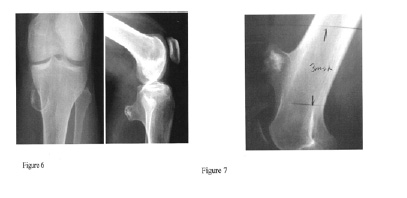

Legs and Knees

Genu Valgum or Knock-knee deformities are found in 8-33% of patients with MHE. Genu valgum is defined as a mechanical malalignment of the lower limb when the knees knock against each other and the legs are pointed away from the body. Although distal femoral involvement is common, the majority of cases of angular limb deformities are due mostly to lesions of the tibia and fibula (Figures 8,9 & 10), which occur in 70-98% and 30-97% of cases, respectively. The fibula has been found by Nawata et al. to be shortened disproportionately as compared to the tibia, and this is likely responsible for the consistent valgus direction of the deformity. Genu varum or Bowlegs may also occur in some cases. This is defined as a mechanical malalignment of the lower limb when the knees drift away from the body and the legs are bowed and close together.

Diagnostic Procedures: The orthopedist will probably manually feel for exostoses along the leg, and check range of motion (“ROM”) by manipulating (moving) the leg in different directions. The orthopedist will also check measurements on each leg to see if there is a difference. X-rays or other imaging tests may be ordered.